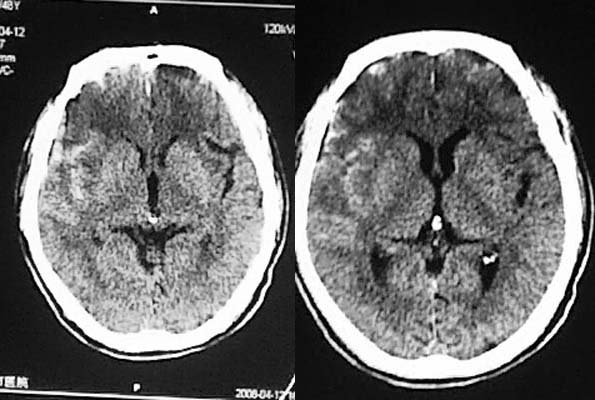

相信各位都会看这种外伤片,发这个帖子的目的在于请大家讨论右侧额、颞叶交界去的低密度到底是脑挫裂伤还是外伤导致周围血管闭塞引起的脑梗塞,请说出理由!!

虽然图片不是很理想,但已经够我们诊断了。请大家一起讨论,一起提高,非常感谢。

相信同行们大部分支持脑挫裂伤,不排除蛛血引起血管痉挛所致脑梗塞,如果要很定那项诊断,还建议增强或mri检查。

左额/顶部硬膜下积液,蛛血,右额叶病灶第一次有高密度影,应该是脑挫裂伤,外伤性脑梗塞应该在第一次照片上就出现.

支持脑挫裂伤

支持脑挫裂伤,图片质量太差